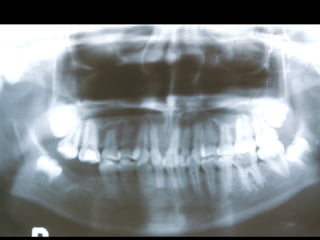

Diagnóstico por Imágenes

• Rx Extraorales: Teleradiografías y

Ortopantomografías

• Rx intraorales: Oclusales y Rx. Periapicales.

• Fundamentalmente Tomografías

Rx Panorámica

Distorciónes en Diferentes Sectores de la Panorámica

En Sentido Vertical

30 %30 %

Sector

Anterior

10 %10 %

Posterior

Distorciónes de la Panorámica

En Sentido Horizontal

Hasta un 70 %Hasta un 70 %